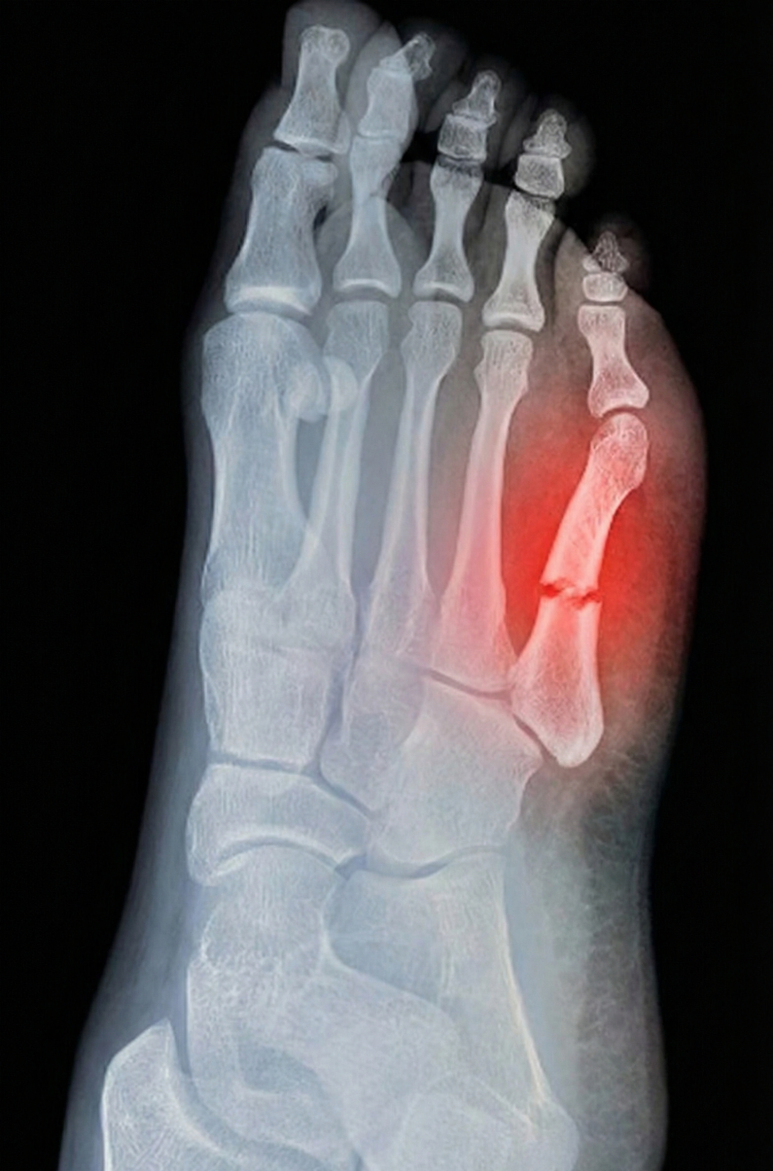

발가락 뼈 실금, 미세골절, 견열골절은

초기 엑스레이(X-ray) 검사에서

발견되지 않을 확률이

무려 40-50%에 달합니다.

특히 다친지 며칠 지나지 않아

엑스레이 검사를 했다면

안 나올 확률이 더 높죠.

뼈가 어긋나지 않고

실금만 똑 간 경우

2차원적인 엑스레이 평면 영상에서는

안 보일 수 있어요.

금 간 부위에서

피가 나고 부으면서

1-2주 지나 골절된 틈이 벌어져야

엑스레이에서 잘 보이거든요.

이런 골절을

잠재 골절, occult fracture

이라고도 합니다.

견열골절 Avulsion fracture도

뼈 조각이 매우 작기 때문에

더더욱 잘 안 보이죠.

뼈 조각이 2mm가 안 되는 경우

CT 에서도 안 보일 수 있습니다.